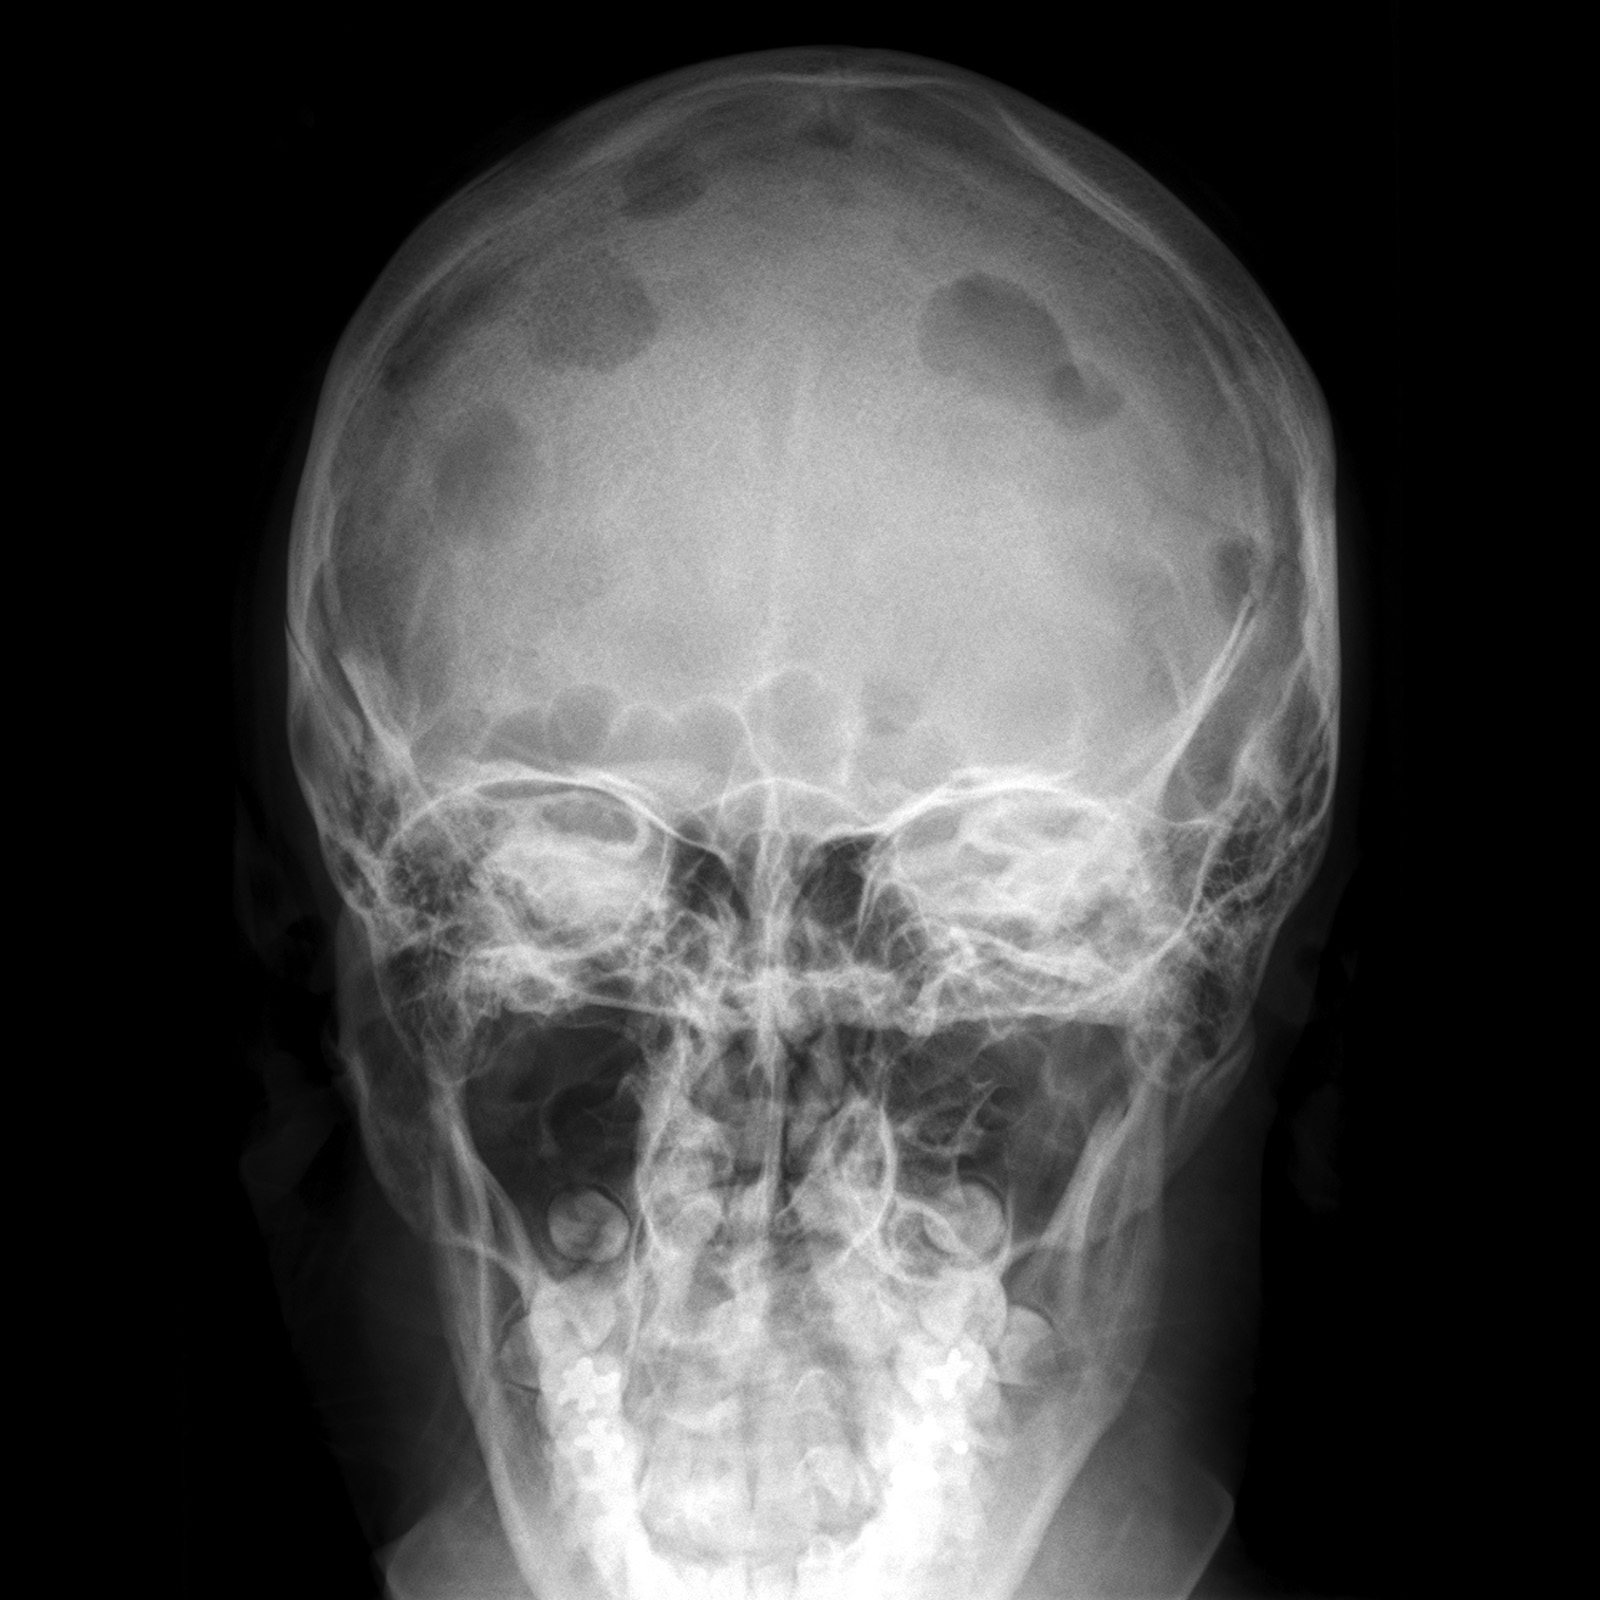

Рентгенография черепа и позвоночника: изображение и диагностика